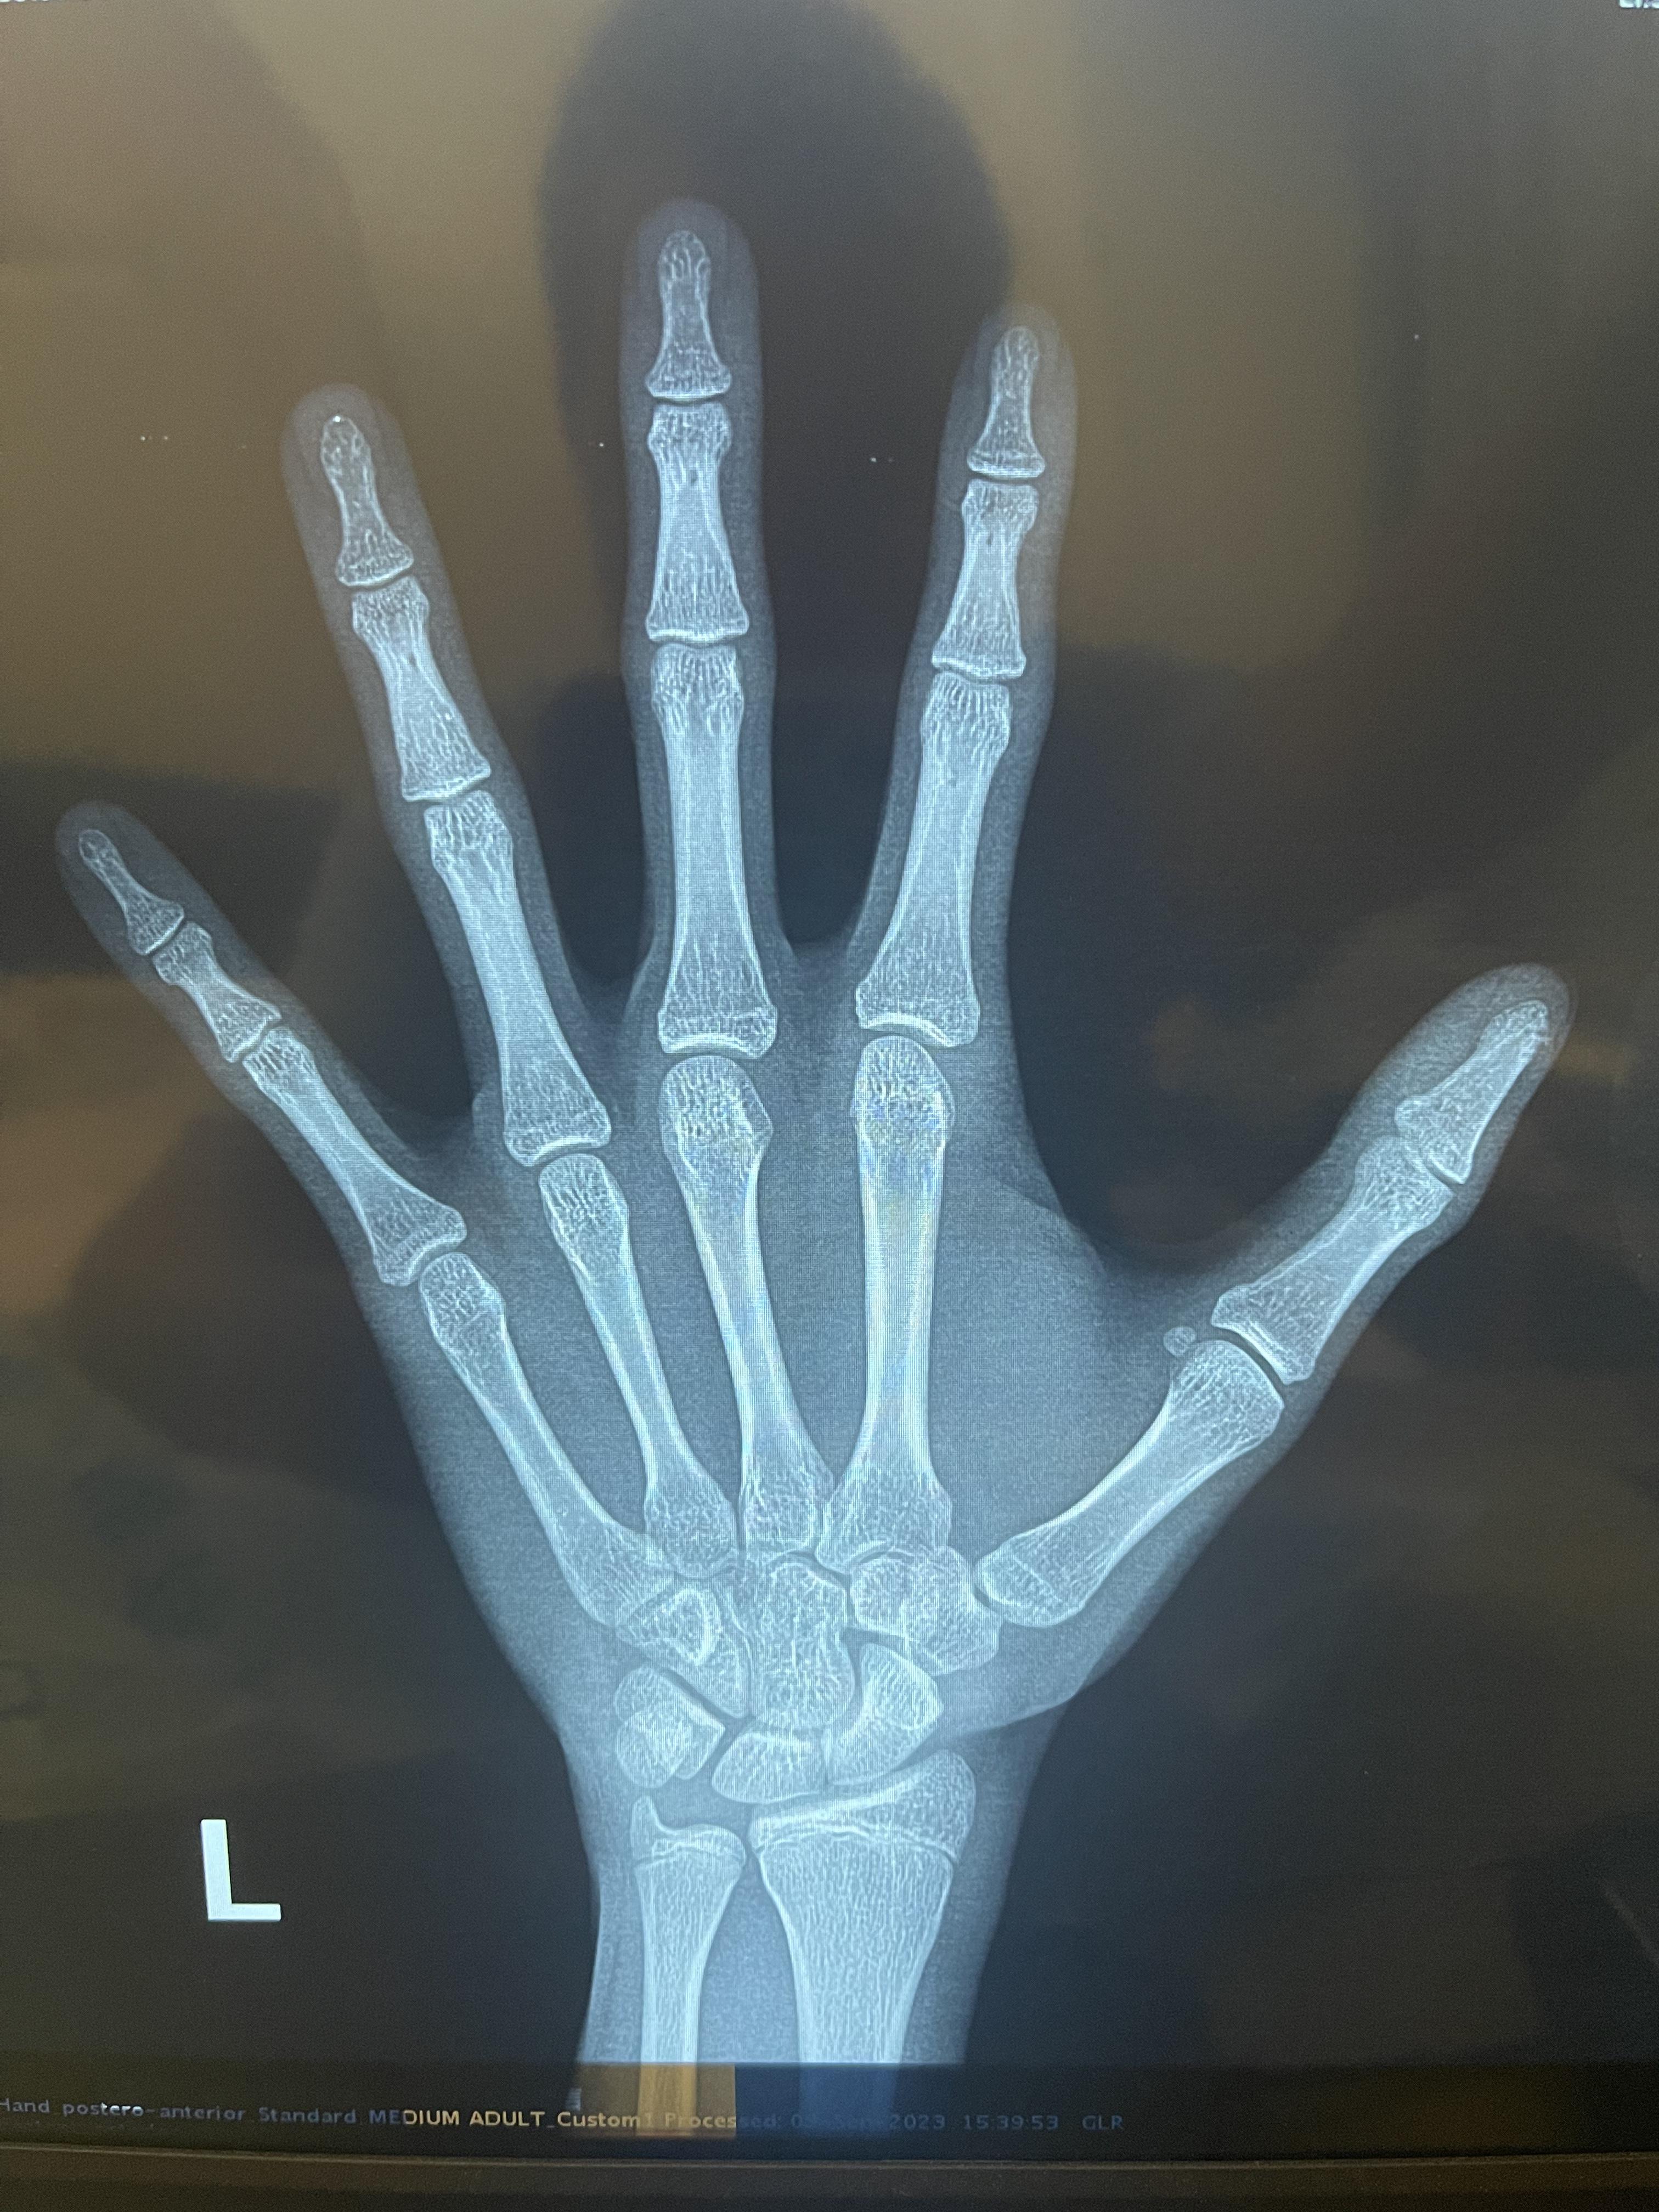

真实照片骨龄成人骨龄片骨龄片未成年骨头和成年骨头ct图长什么样子

图片尺寸800x1200